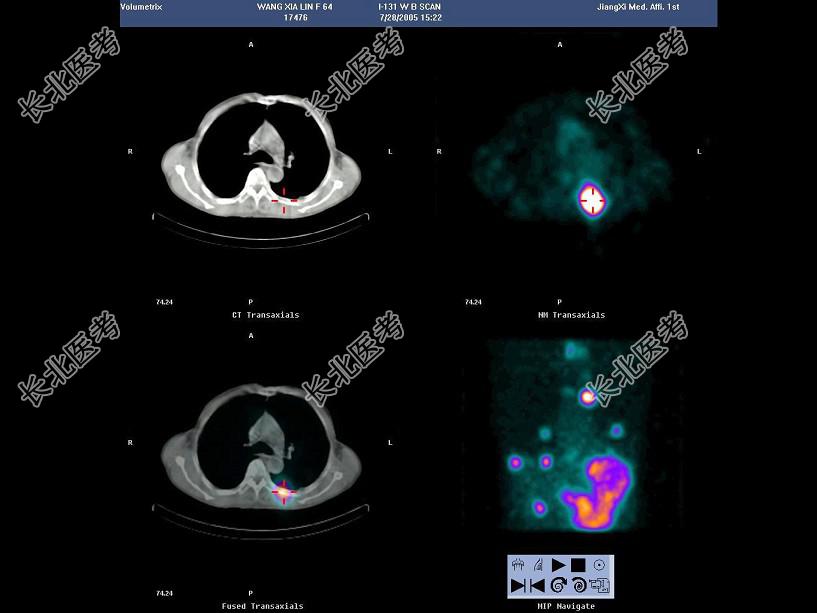

- 多项选择题63岁男性患者,甲状腺滤泡状癌术后3年, 行131I全身显像及SPECT/CT图像融合如图,正确的诊断是 ( )

B、有骨转移

E、多发肺转移